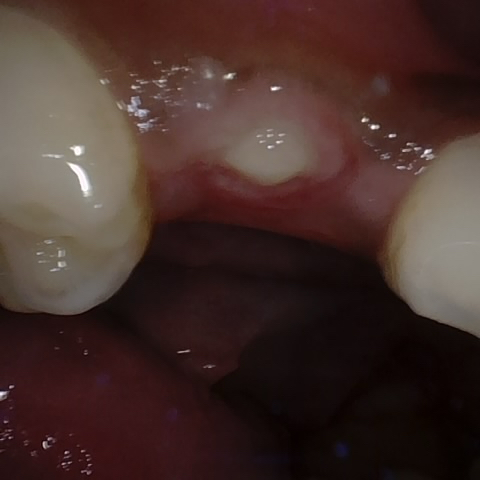

Annotated as "Good"